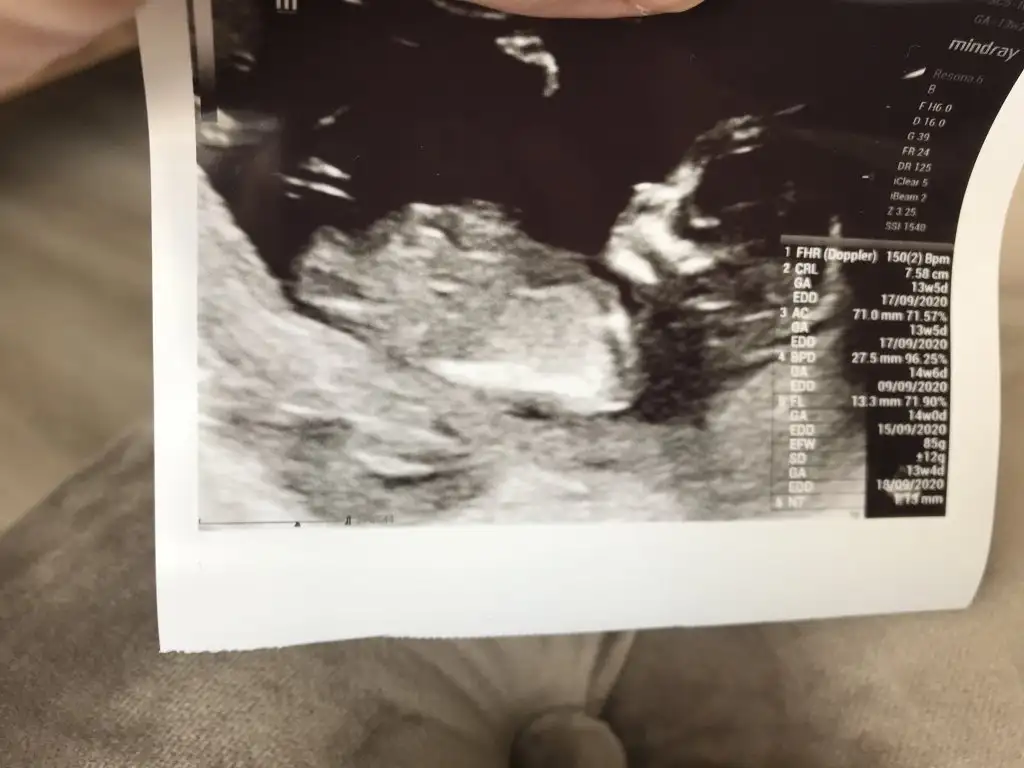

merhaba 12 haftalık hamileyim bende bugün ikili tarama yaptırdım cinsiyet tahmininizi alabilir miyim :)

Eklentiler

• E5C92BC7-7E7F-4A45-8611-64A3B20844EA.webp

E5C92BC7-7E7F-4A45-8611-64A3B20844EA.webp

40,6 KB · Görüntüleme: 51